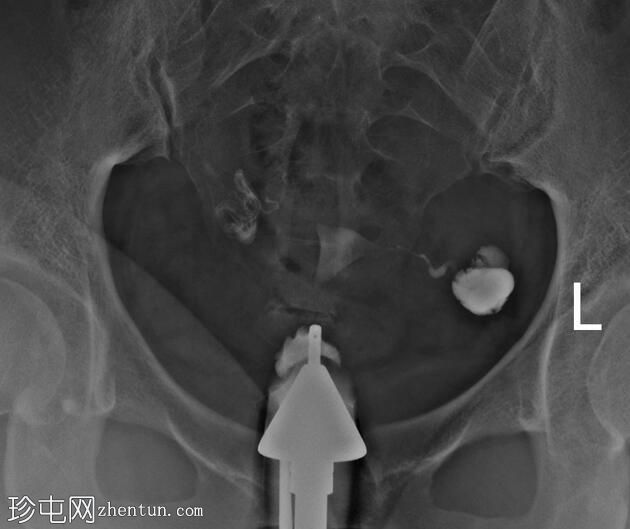

子宫体位于盆腔中线,形态及轮廓正常。

宫颈管长度正常,黏膜表面扩张良好。

右侧输卵管扩张并充满液体,无腹膜溢出,提示输卵管积水及输卵管阻塞。

左侧输卵管亦扩张并充满液体,伴有造影剂残留及少量溢出,提示输卵管积水及输卵管阻塞。

此外,左侧盆腔内,位于输卵管上内侧,可见大量分隔的造影剂积聚,并伴有盆腔输卵管周围粘连。

子宫输卵管造影结果符合双侧输卵管阻塞和输卵管积水,左侧输卵管周围可见分隔的造影剂渗漏。